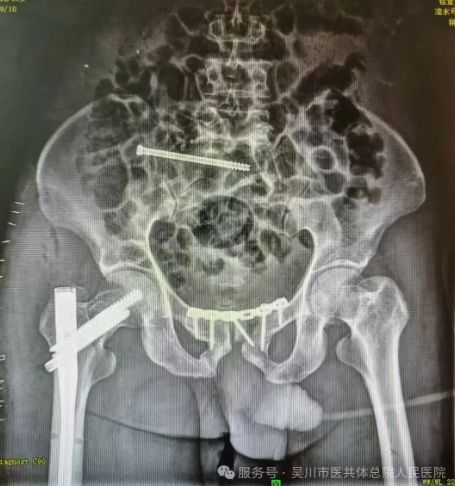

骨外科一区主任、主任医师李德强,立即带领专家团队对患者的各项身体指标、受伤情况等进行综合评估,缓解家属的焦虑情绪。最终决定为患者施行损伤控制手术,稳定患者的生命体征,待其血流动力学稳定后,再二期采用微创小切口的方式来修复骨盆以及股骨多段骨折。